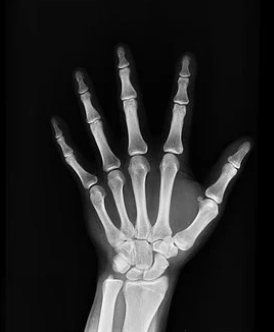

대부분의 뼈는 원형이 만들어진 후 그 일부분에서 뼈로 변화되는데 관절부위 만은 연골로 남아있다가 연골이 점차 뼈로 변화되는데 마지막에 남은 얇은 원판을 성장판이라고 하며, 이 성장판이 열려 있는지 닫혀있는지 여부에 따라 앞으로 키가 얼마나 더 클 수 있을지를 알 수 있습니다.

보통 성장판은 손목이 가장 빨리 닫힙니다. 일반적으로 성장판 닫히는 순서는 손목, 어깨, 팔꿈치, 무릎, 발목, 손가락, 발가락 뼈들입니다.

그러나 손목이 아닌 아직 다른 곳이 열려있다면 아직 키가 클 가능성이 충분히 있죠. 그중에서 최종키를 결정짓게하는 가장 중요한 성장판은 발목이나 무릎의 성장판입니다.